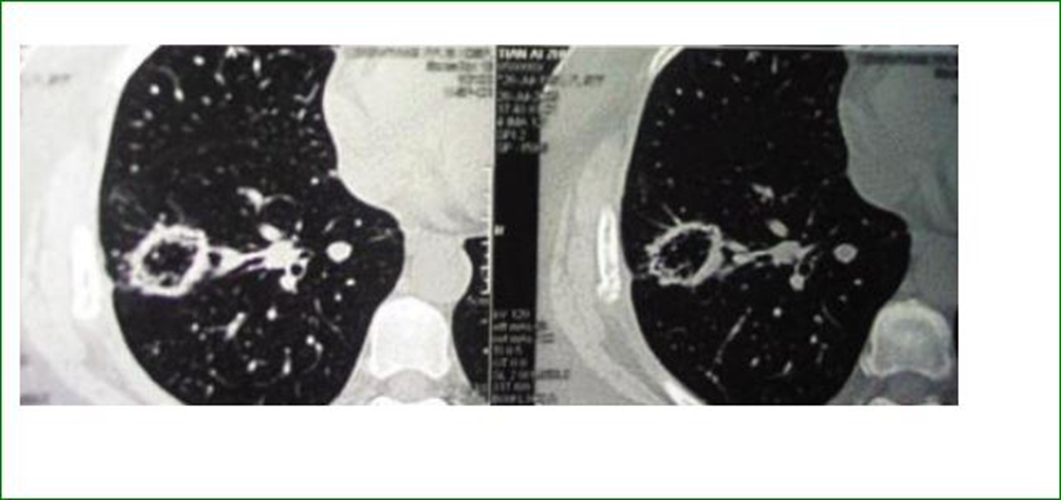

右上肺腺癌